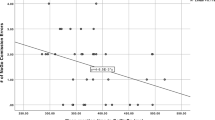

Whole brain voxel-wise permutation analyses revealed a reduction of FA and an increase of MD, RD, and DA throughout the whole brain in NF1 adolescents when compared to controls (Fig. 2). Correlation analyses in NF1 patients revealed an association between the averaged values of the MD and inhibitory control (r = .646, CIbootstrap = 0.034–0.882), and the averaged values of the DA and inhibitory control (r = .673, CIbootstrap = 0.272–0.861) (Fig. 3). No significant correlation was identified for the averaged values of the whole brain DTI metrics and our estimates of verbal, performance and total abilities.

No DTI-measure of the CB or the SLF revealed a significant correlation with our measure of inhibitory control in NF1 patients (CB: FA left: r = −.203, CIbootstrap = −.785–.424; FA right: r = −.307, CIbootstrap = −.776–.349; MD left: r = .350, CIbootstrap = .-483–.879; MD right: r = −.009, CIbootstrap = −.769–.653; RD left: r = .472, CIbootstrap = −.366–.823; RD right: r = .099, CIbootstrap = −.659–.709; DA left: r = .093, CIbootstrap = −.477–.731; DA right: r = −.131, CIbootstrap = −.778–.595; SLF: FA left: r = .055, CIbootstrap = −.583–.720; FA right: r = −.187, CIbootstrap = −.725–.483; MD left: r = .241, CIbootstrap = .-512–.712; MD right: r = .406, CIbootstrap = −.594–.902; RD left: r = .111, CIbootstrap = −.643–.583; RD right: r = .331, CIbootstrap = −.456–.790; DA left: r = .280, CIbootstrap = −.387–.785; DA right: r = .347, CIbootstrap = −.286–.772). In contrast, for the ATR associations with inhibitory control were evident for FA (r = −.405, CIbootstrap = −0.752-(−0.060); not significant after correction for multiple comparisons), MD (r = .707, CIbootstrap = 0.196–0.930), and RD (r = .771, CIbootstrap = 0.490–0.919), all in the left hemisphere (Fig. 3). No significant correlations between FA, MD, RD, and DA of the CB, the SLF or the ATR and our IQ-estimates were found.